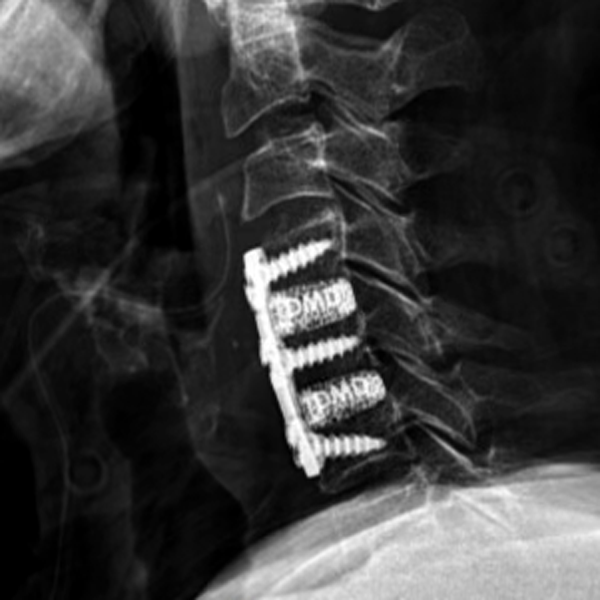

Frameless cervical cages made out of color-coded Titanium

Machined Metal

Too rigid

Subsidence issues

Not for osteoporotic bone

Ti-Coated PEEK

Osteo-phobic

Osteo-conductive top & bottom only